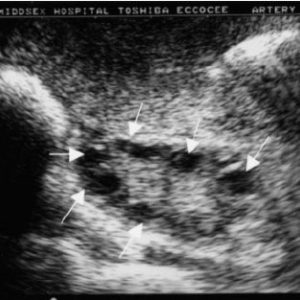

Let’s say you’re looking at an ultrasound of a PCOS patient, and there are cysts present. One or both ovaries will contain small, immature ovarian follicles. These follicles will show up in medical imaging as cysts.

With PCOS, ovarian follicles stay in an immature state because of abnormal hormone levels present in the person’s body. These follicles can’t grow to their fully matured state where an egg would normally be released. Instead, the immature follicles accumulate in the person’s ovaries.

Some people have 12 or more cysts present in their ovaries. The good news is that the number of cysts you have tends to decrease with age. And, symptoms can often be improved through medical help and lifestyle adjustments.